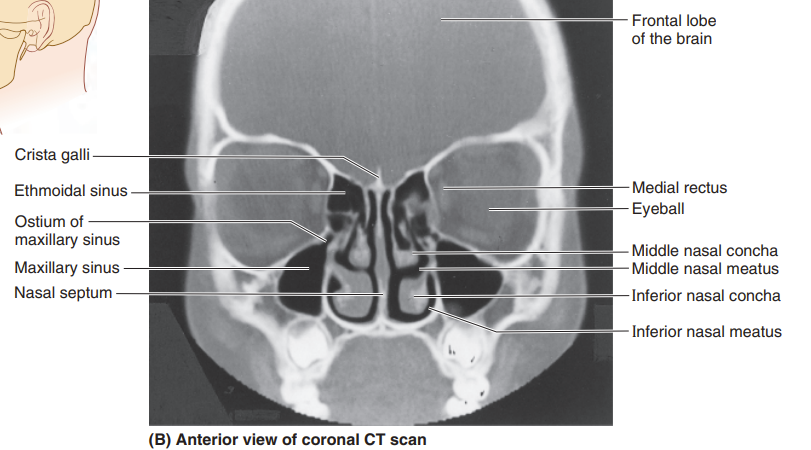

Please label this coronal CT scan